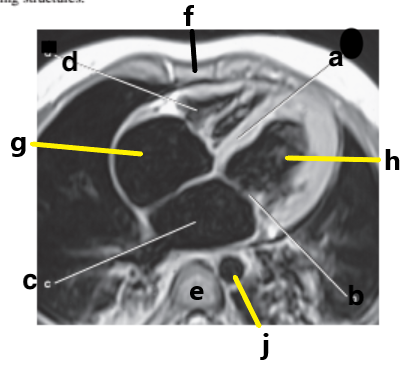

What is letter a ?

Right ventricle

What is letter h ?

Left ventricle

What is letter d ?

What is letter c ?

Hemiazygos vein

Which letter is the Right coronary artery ?

c

Left anterior descending artery